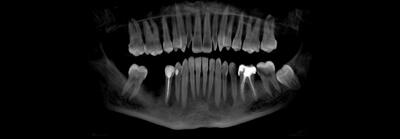

Я подготовился к приему заранее, посмотрел компьютерную томографию, которую он мне прислал.

По снимку видно, что необходим комплексных подход к проблеме, который будет включать в себя мою работу, как хирурга, так и смежных специалистов. Гигиениста, ортопеда и терапевта.

Вот так было: